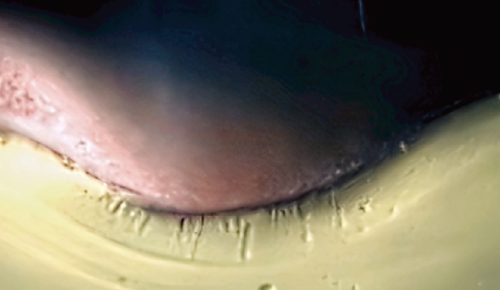

固体(アイス・ニードリング) VS 液体浸透比較

個体(アイス・ニードリング)

氷の粒子は衝突時に変形されずに表面を通り抜けます。これにより、薬剤を皮内へ浸透させることが可能です。

液体

液体は衝突時に変形されて表面から飛び跳ねます。よって、薬剤が液状で皮膚表面に残るようになります。

アイス・ニードリングは、表皮と真皮の境界にあたる表皮真皮接合部(DEJ)を正確にターゲットとしています。ターゲットクールを用いて希望の薬剤を導入することで、薬剤成分が表皮から真皮にかけて作用し、より効率的かつ素早い効果を実感いただけます。